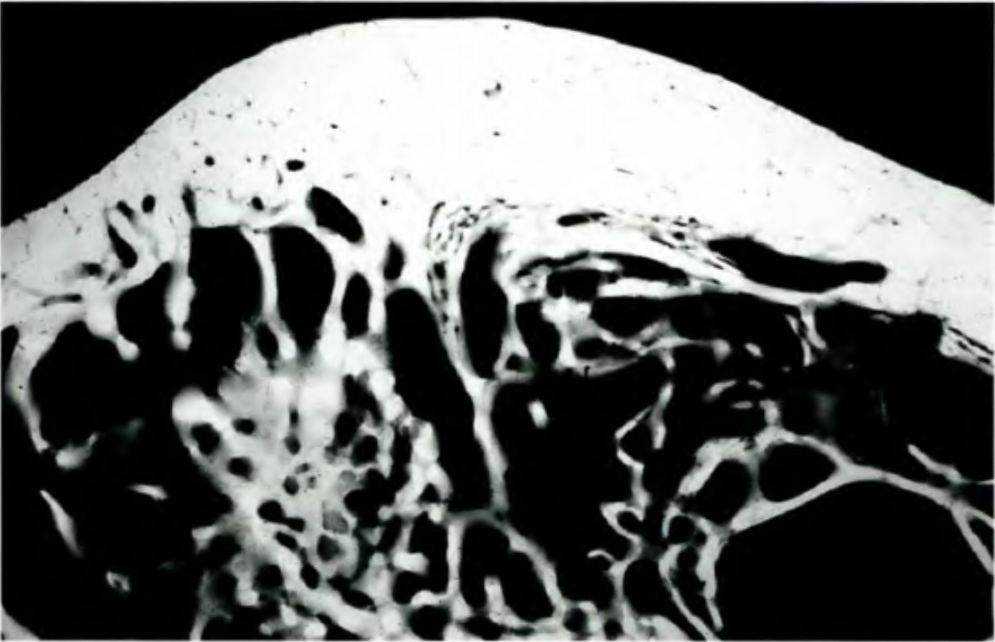

Рис. 5-4. Пористая костная ткань типа D4 (с разрешения проф. Klaus-Ulrich Веппег, Мюнхенский институт анатомии)

Рис. 5-9. Внутренняя атрофия кости приводит к образованию полостей в толще ткани